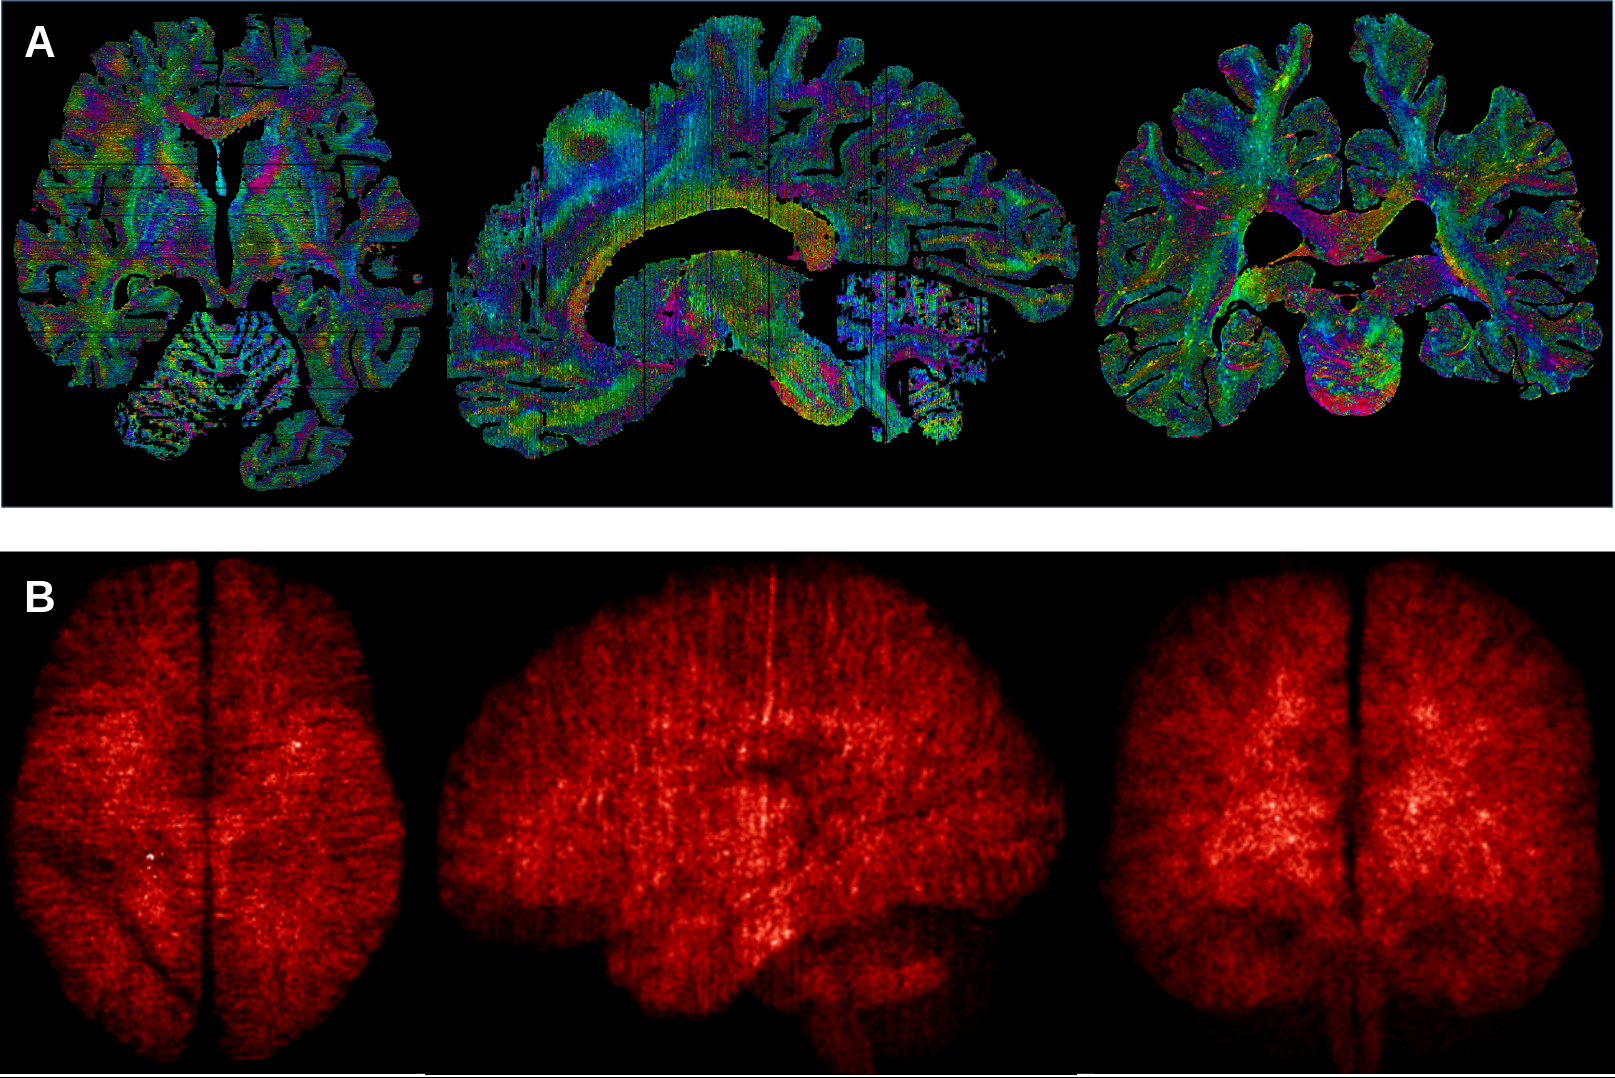

An exhaustive map of the human brain has been a long-sought goal of neuroanatomists. Noninvasive imaging techniques such as magnetic resonance imaging (MRI) allow scientists to investigate the healthy living human brain but provide only limited anatomical detail. A higher level of detail can be obtained by using microscopy on brains from deceased donors, generally focusing on small brain structures imaged in 2D. Now a team led by scientists from the UvA, have combined MRI and microscopy to produce 3D images of two entire brains with a previously unmatched level of detail. Their findings have been published in the journal Science Advances.

The UvA team worked for over five years, alongside researchers from the Max Planck Institute in Leipzig, to build a bridge between ultra-high field MRI and microscopy approaches to creating images of the brain. Two human brains donated to science were placed in the MRI scanner for 21 hours, and afterwards examined under the microscope. The MRIs were then combined with the microscopy slides, resulting in images of the brains which allow for exploration at a 200mm (0.2mm) level of detail.

The researchers used an ultra-high field 7 Tesla MRI system, which has a more powerful magnet than the MRI systems routinely used in hospitals. The MRI software was programmed specifically for these studies by the researchers to accommodate the differences between living and preserved tissue. During the cutting of the tissue, each section was photographed individually, so that it could be used later to digitally correct tissue deformation in microscopy sections. Individual brain sections were placed on specially ordered glass slides, and processed with custom-built laboratory equipment.

After digitisation of the individual microscopy slides, new algorithms were created by the researchers to correct for the tissue deformation resulting from the cutting and microscopy processing. After weeks of uninterrupted calculations, the researchers were finally able to create full reconstructions of two individual brains.